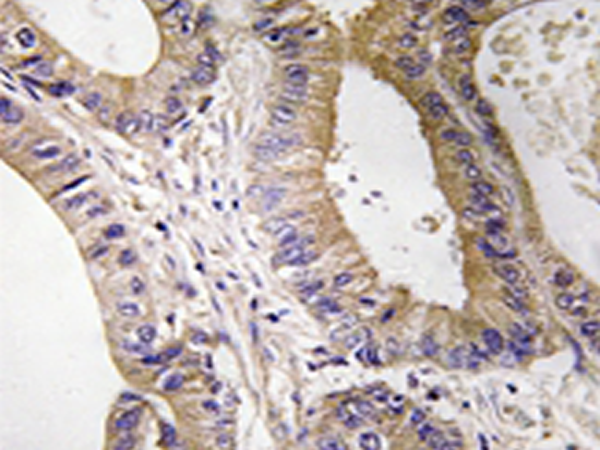

IHC positive control: |

Human colon carcinoma tissue |

IHC Recommend dilution: |

50-100 |